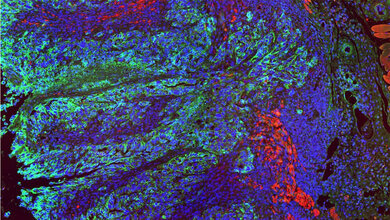

In der Krebsmedizin wird zudem für viele Menschen die Translation neuer Erkenntnisse in die Versorgung direkt sichtbar. So sind für einige Krebserkrankungen Immuntherapeutika in Deutschland bereits in der Routine angekommen.